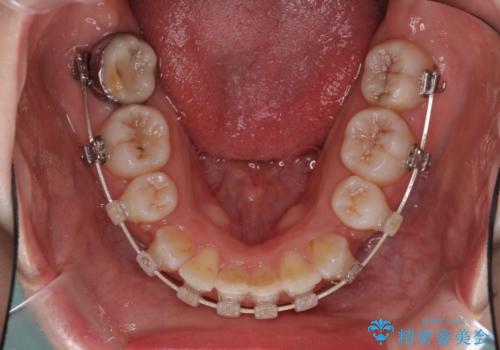

- ハーフリンガル

目立たない装置を希望されたので、上顎が裏側装置のハーフリンガルを選択し、上下左右の小臼歯(計4歯)を抜歯して矯正治療を行うこととしました。

治療期間の目安は2年半~3年間でしたが、咬み合わせにより上顎装置が頻繁に脱落してしまい、治療期間が長期化してしまいました。